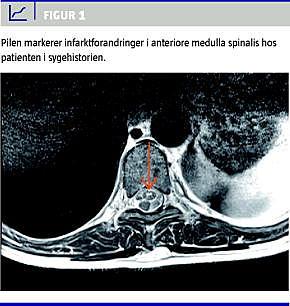

En 42-årig mand med polycystisk nyresygdom og medicinsk behandlet hypertension fik divertikulitis og undergik partiel kolektomi i generel anæstesi. Operationen forløb ukompliceret. Postoperativt blev der anlagt epiduralkateter på Th 10-niveau mhp. smertelindring. Der blev injiceret bupivacain/morfin 4 ml/t. I løbet af operationsdagen fik patienten vedvarende hypotension med middelarterieblodtryk (MAP) på 55-60 mmHg, som blev tilskrevet den epidurale anæstesi og behandlet med vasopressorer, indtil MAP var over 60 mmHg. Epiduralkateteret blev derfor seponeret på den første postoperative dag. På dette tidspunkt oplyste patienten, at han ikke havde kunnet bevæge begge underekstremiteter (UE) postoperativt, men han tilskrev det epiduralkateteret og havde derfor ikke nævnt det tidligere. Ved en neurologisk undersøgelse på den anden postoperative dag fandt man normale forhold på begge overekstremiteter. På truncus fandtes nedsat sensibilitet ved Th10 og ophævet temperaturfølsomhed kaudalt herfor. På UE fandt man varierende kraftnedsættelse i alle led, nedsat sensibilitet, ophævet evne til at skelne mellem spidst og stumpt, ophævet varme/kuldediskrimination og nedsat, men bevaret stillingssans. Man stillede derfor den kliniske diagnose medulla spinalis anterior-syndrom (MSA). På den baggrund havde man mistanke om spinalt infarkt, transversal myelitis eller strukturel skade. Patienten blev overført til Rigshospitalet, og der blev foretaget inkonklusiv magnetisk resonans (MR)-skanning, hvorved formodningen om fokale forandringer blev afkræftet. Trods bedring resterede der en betydelig paraparese efter tre døgn, hvorfor patienten blev indstillet til rehabilitering. Forinden blev der foretaget en ny MR-skanning, hvorved der blev verificeret MSA (Figur 1 ). Seks måneder postoperativt sad patienten fortsat i kørestol.